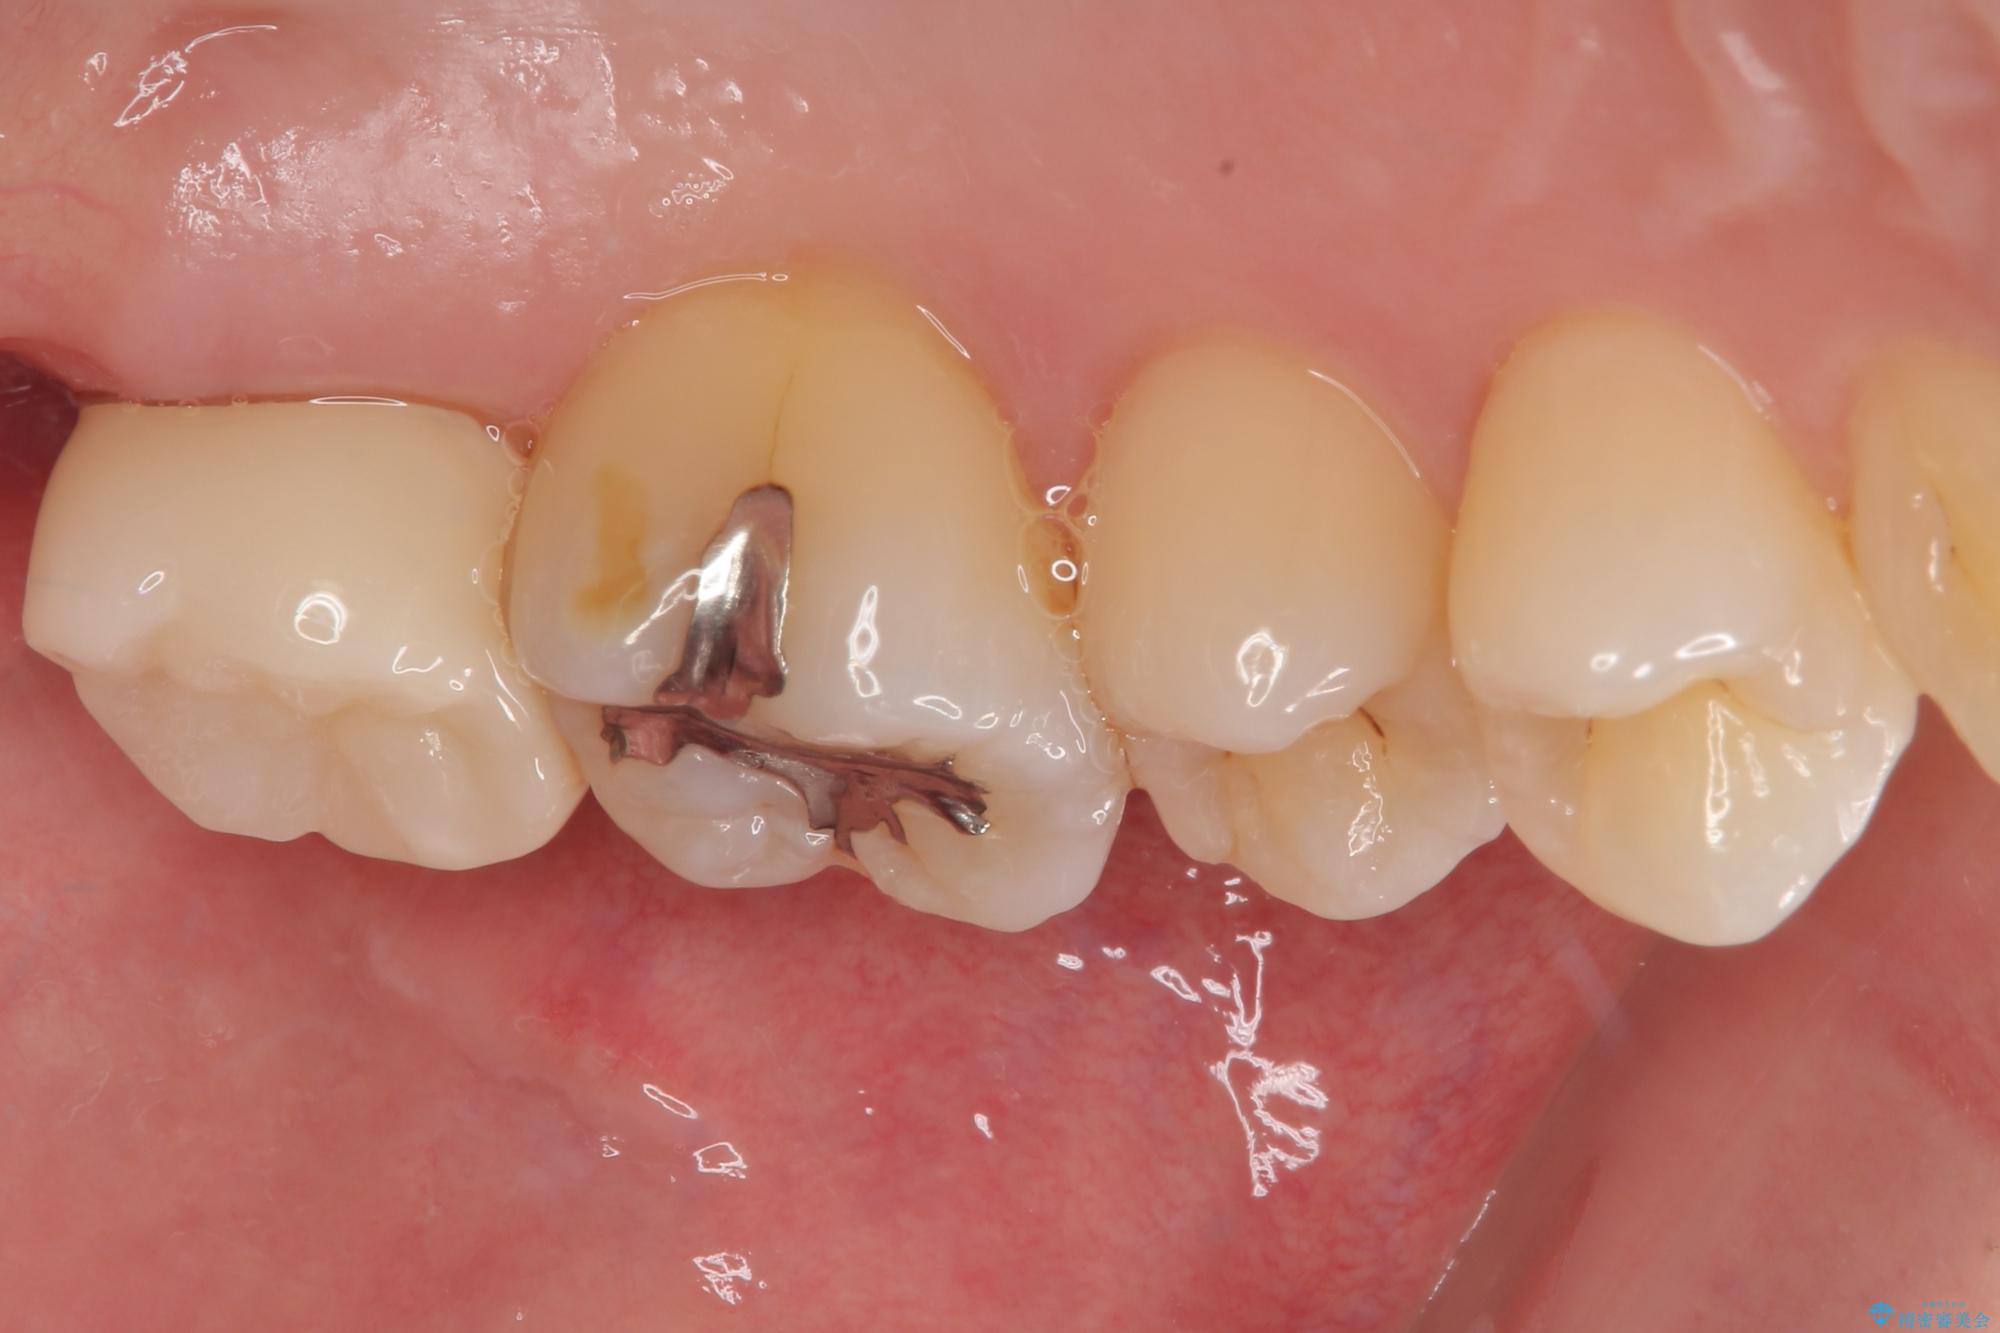

矯正治療により処置が可能な位置に歯が移動したため、オールセラミッククラウンにて補綴治療を行うこととしました。

歯列が移動したとはいえ、左右ともに後方傾斜しており、むし歯の除去、形成(形を整える)、型取りの全てが非常に困難な処置となりました。

セラミッククラウンの適合はレントゲン写真からも分かる通り、境界がぴったりと合った、高適合のものとなりました。